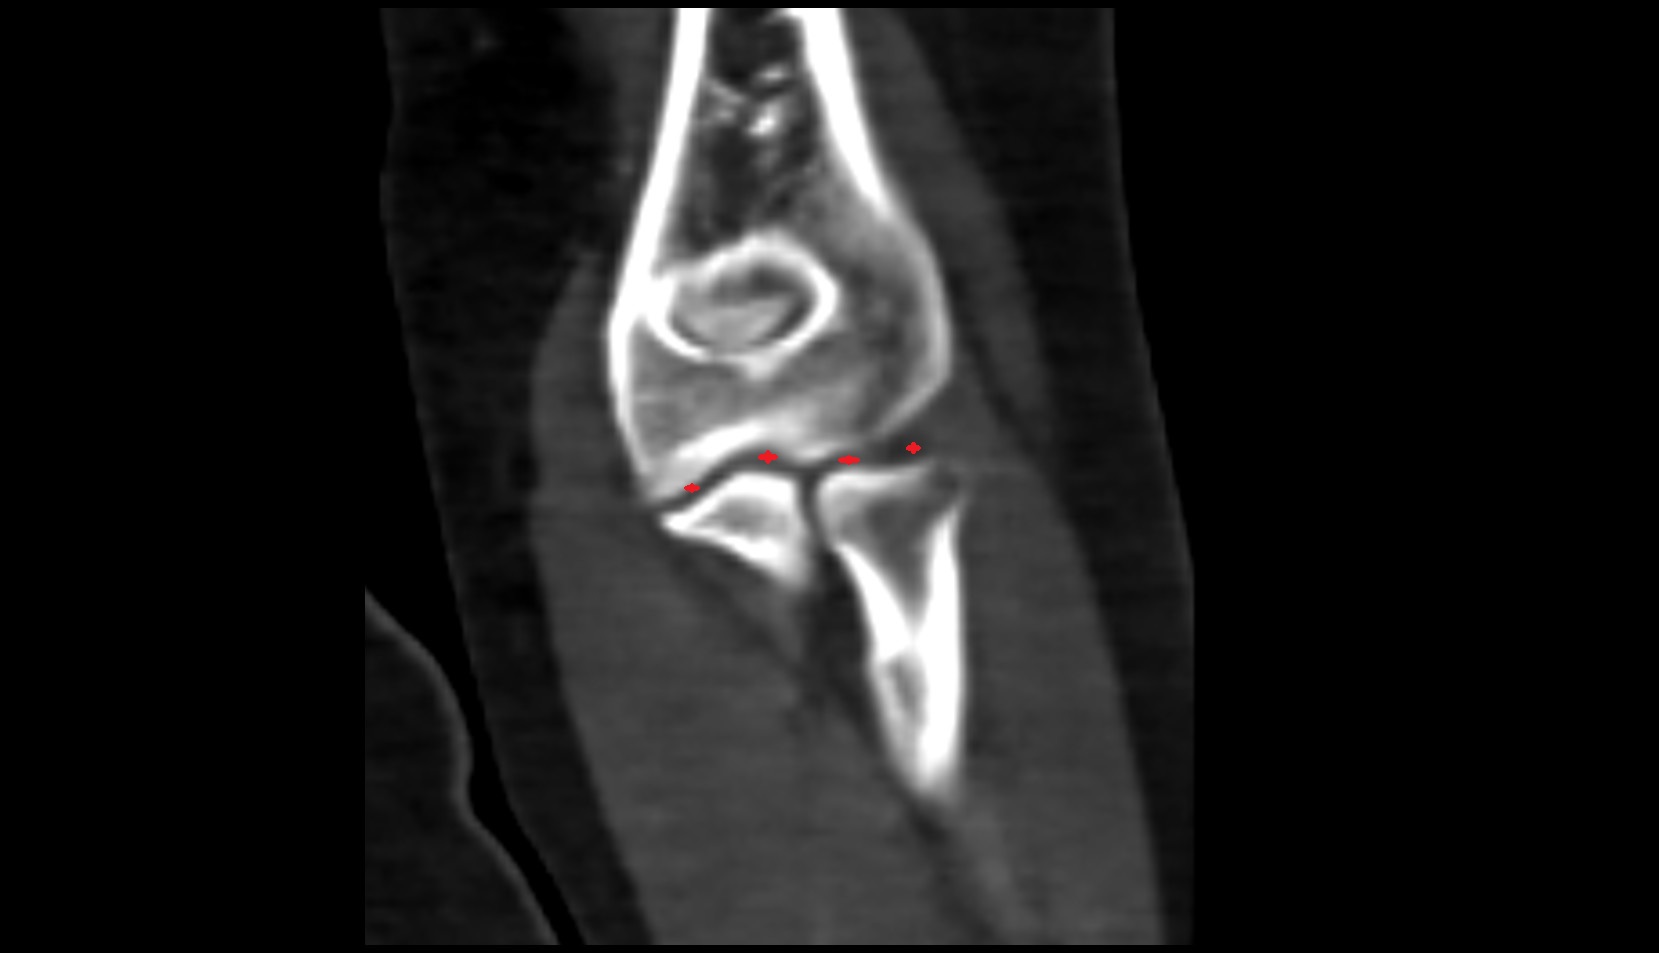

- Elbow joint

- Olecranon fossa

- Olecranon

- Trochlear notch of ulna

- Coronoid fossa